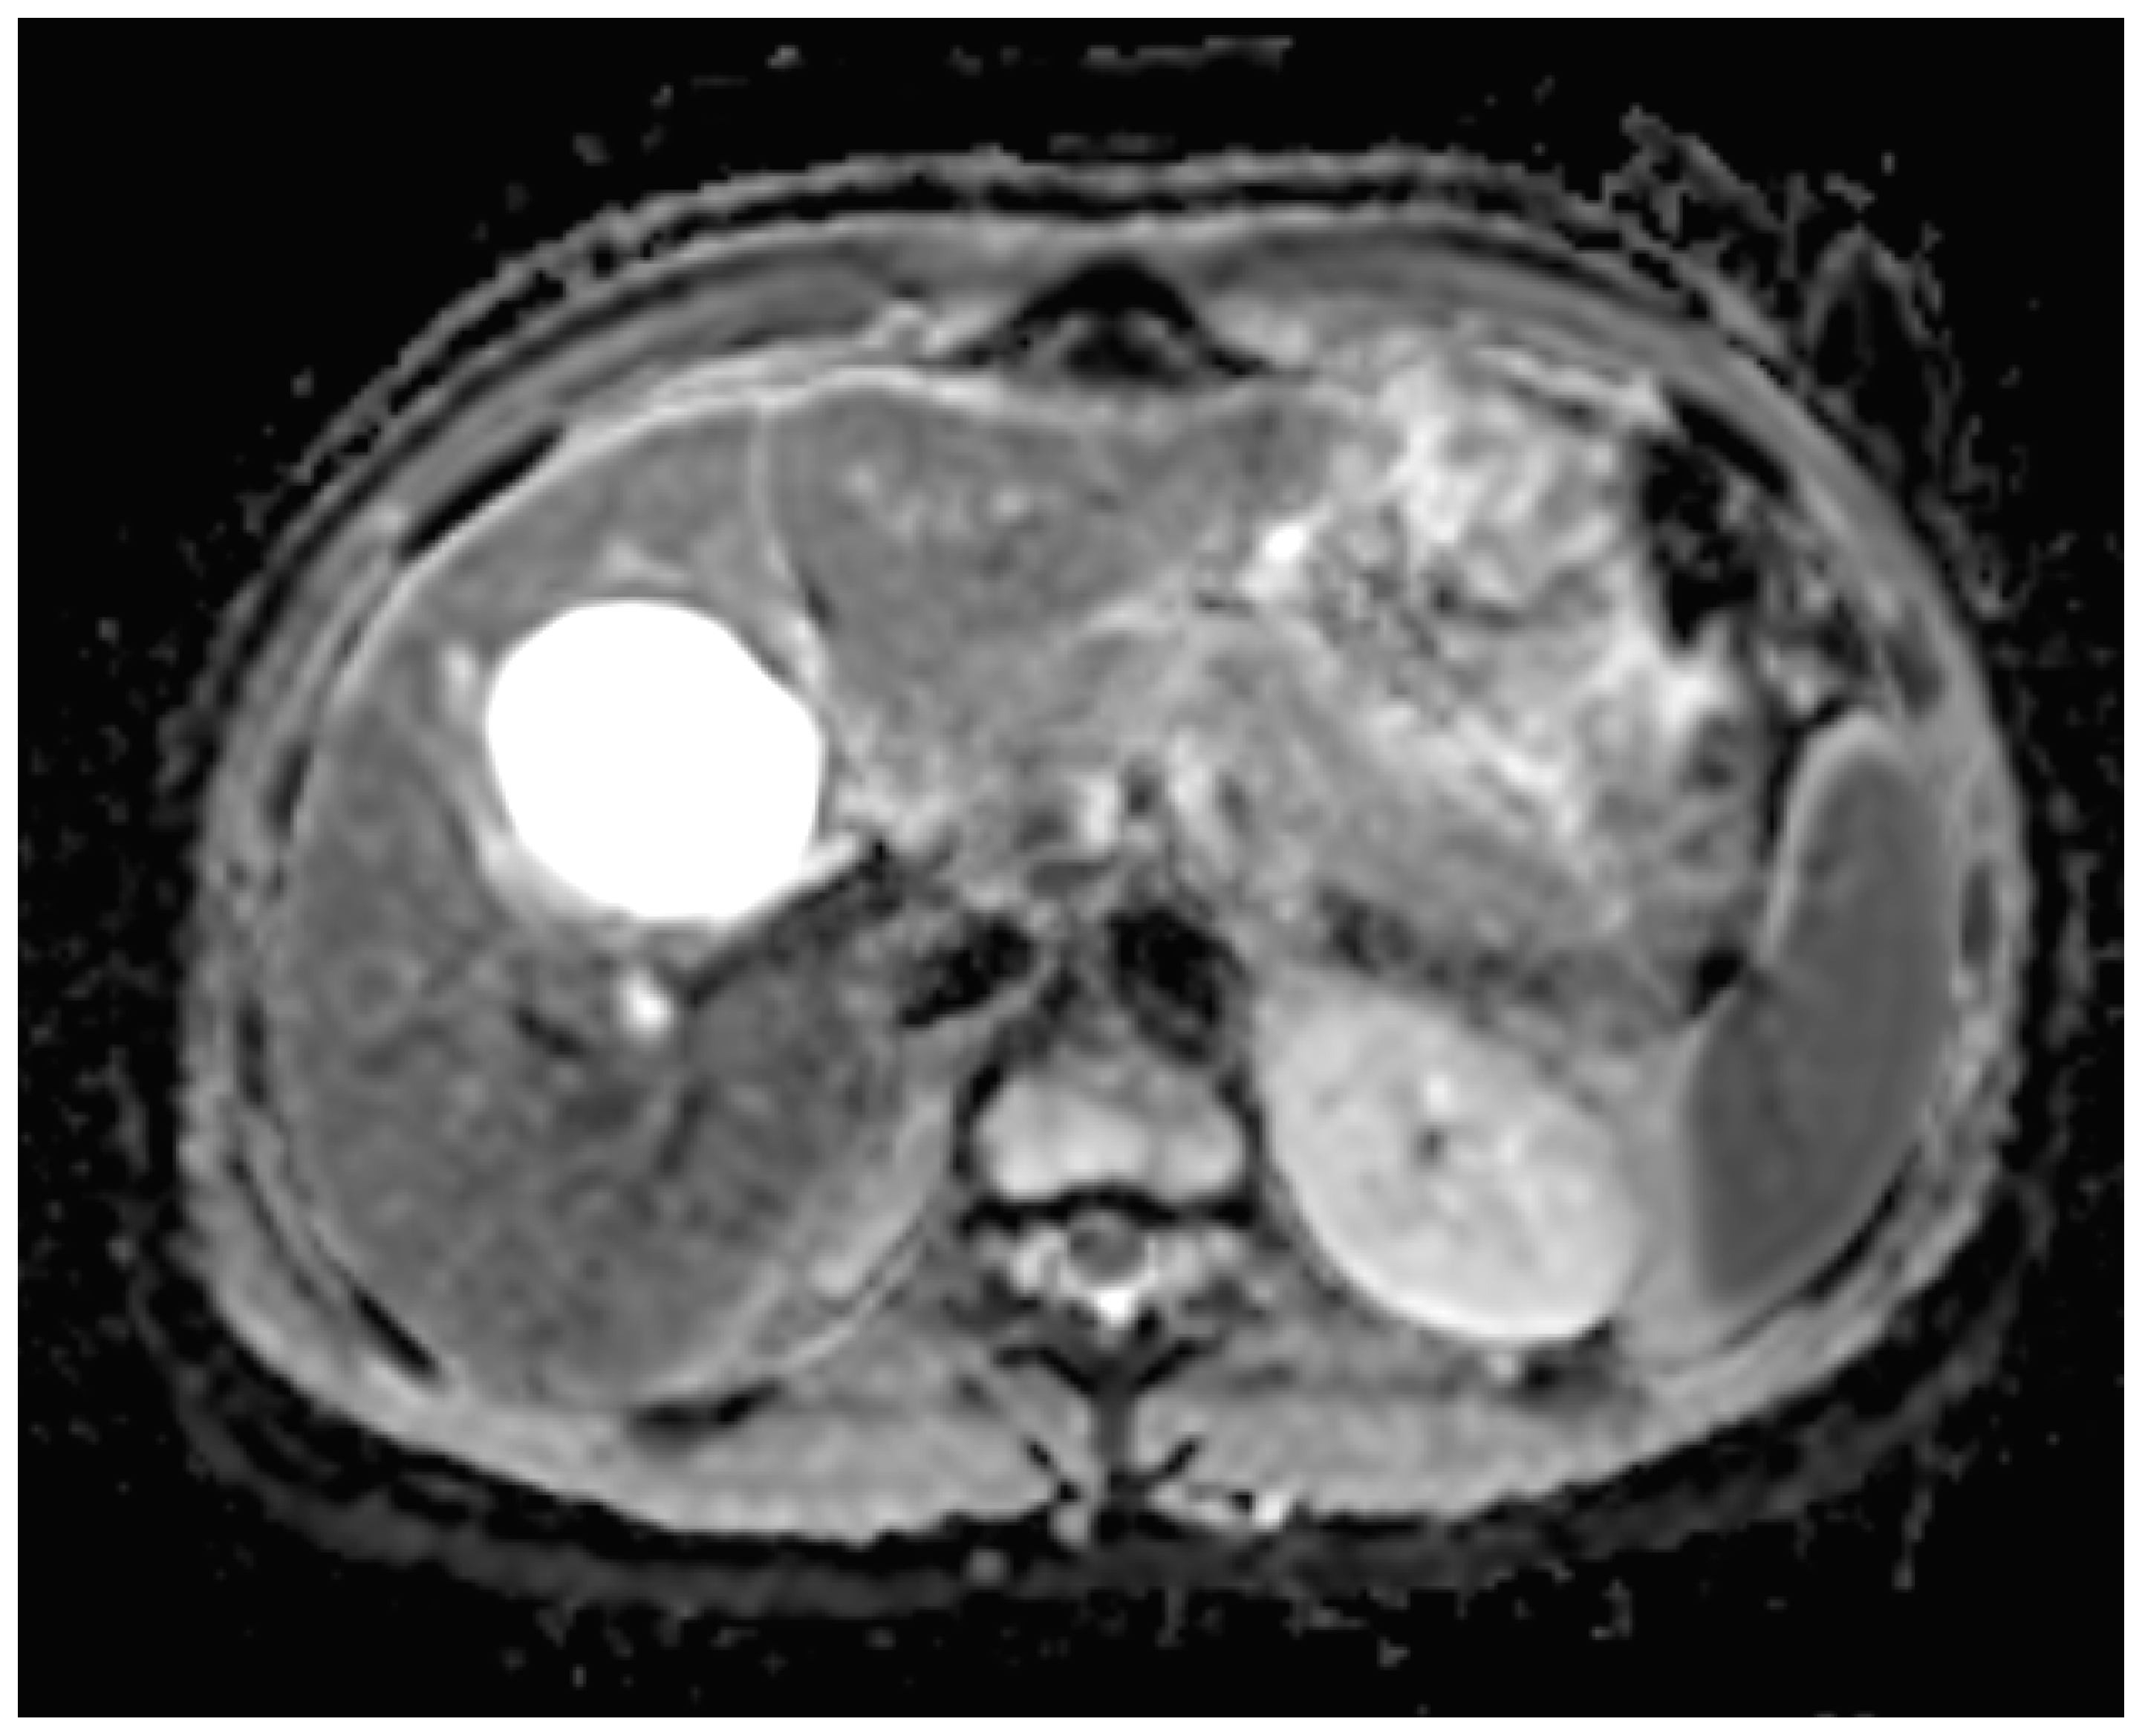

A liver MRI scan confirmed a cystic structure with multiple daughter cysts, hypointense on a T1-weighted image (T1WI), and hyperintense on a T2-weighted image (T2WI), with no solid components, no signs of membrane rupture, and a maximum diameter of 10 cm (craniocaudal) (Figure 1). Additionally, elevated signals on T2WI in the surrounding liver tissue were found. The T1 sequences did not reveal any contrast uptake after 5 (Figure 2), 10, or 20 (Figure 3) minutes post-injection. Furthermore, DWI/ADC mapping indicated a hydatid cyst. The DWI sequences included a trace DWI (Figure 4), an ADC map (Figure 5), and both at b800. Radiomics and AI tools were not involved. The trace DWI showed an area of hypointensity in the region of the cyst that was surrounded by a hypointense layer, depicting the cystic wall. The ADC map revealed hyperintensity within the area, in concordance with a typical depiction of cysts on an MRI scan.

Figure 1.

First MRI scan: Axial T2W MRI scan revealing hyperintense areas in liver segment IV, suspicious daughter cysts, and clearly visible septation.

MR imaging clearly visualizes pericyst, matrix, and daughter cysts. The pericyst appears as a hypointense rim on both T1WI and T2WI due to its fibrous structure and the presence of calcifications. This is a specific feature of hydatid cysts, called the rim sign, mostly better visualized on T2WI [5]. The matrix represents hydatid-fluid-containing membranes of broken daughter vesicles, scolices, and hydatid sand [7]. The hydatid matrix appears hypointense on T1WI and significantly hyperintense on T2WI. However, the limitations of MRI scans are especially observed in stages CE4–CE5, as bigger calcifications are better observed on a CT scan. When daughter cysts are present, they are typically more hypointense than the matrix on T2WI, as observed in our case report [17] (Figure 1). If the membrane is separated, it can shift with movement, resembling a water lily floating on the surface of a pond, previously described as water-lily sign, which was seen in our case report as well [18] (Figure 8).